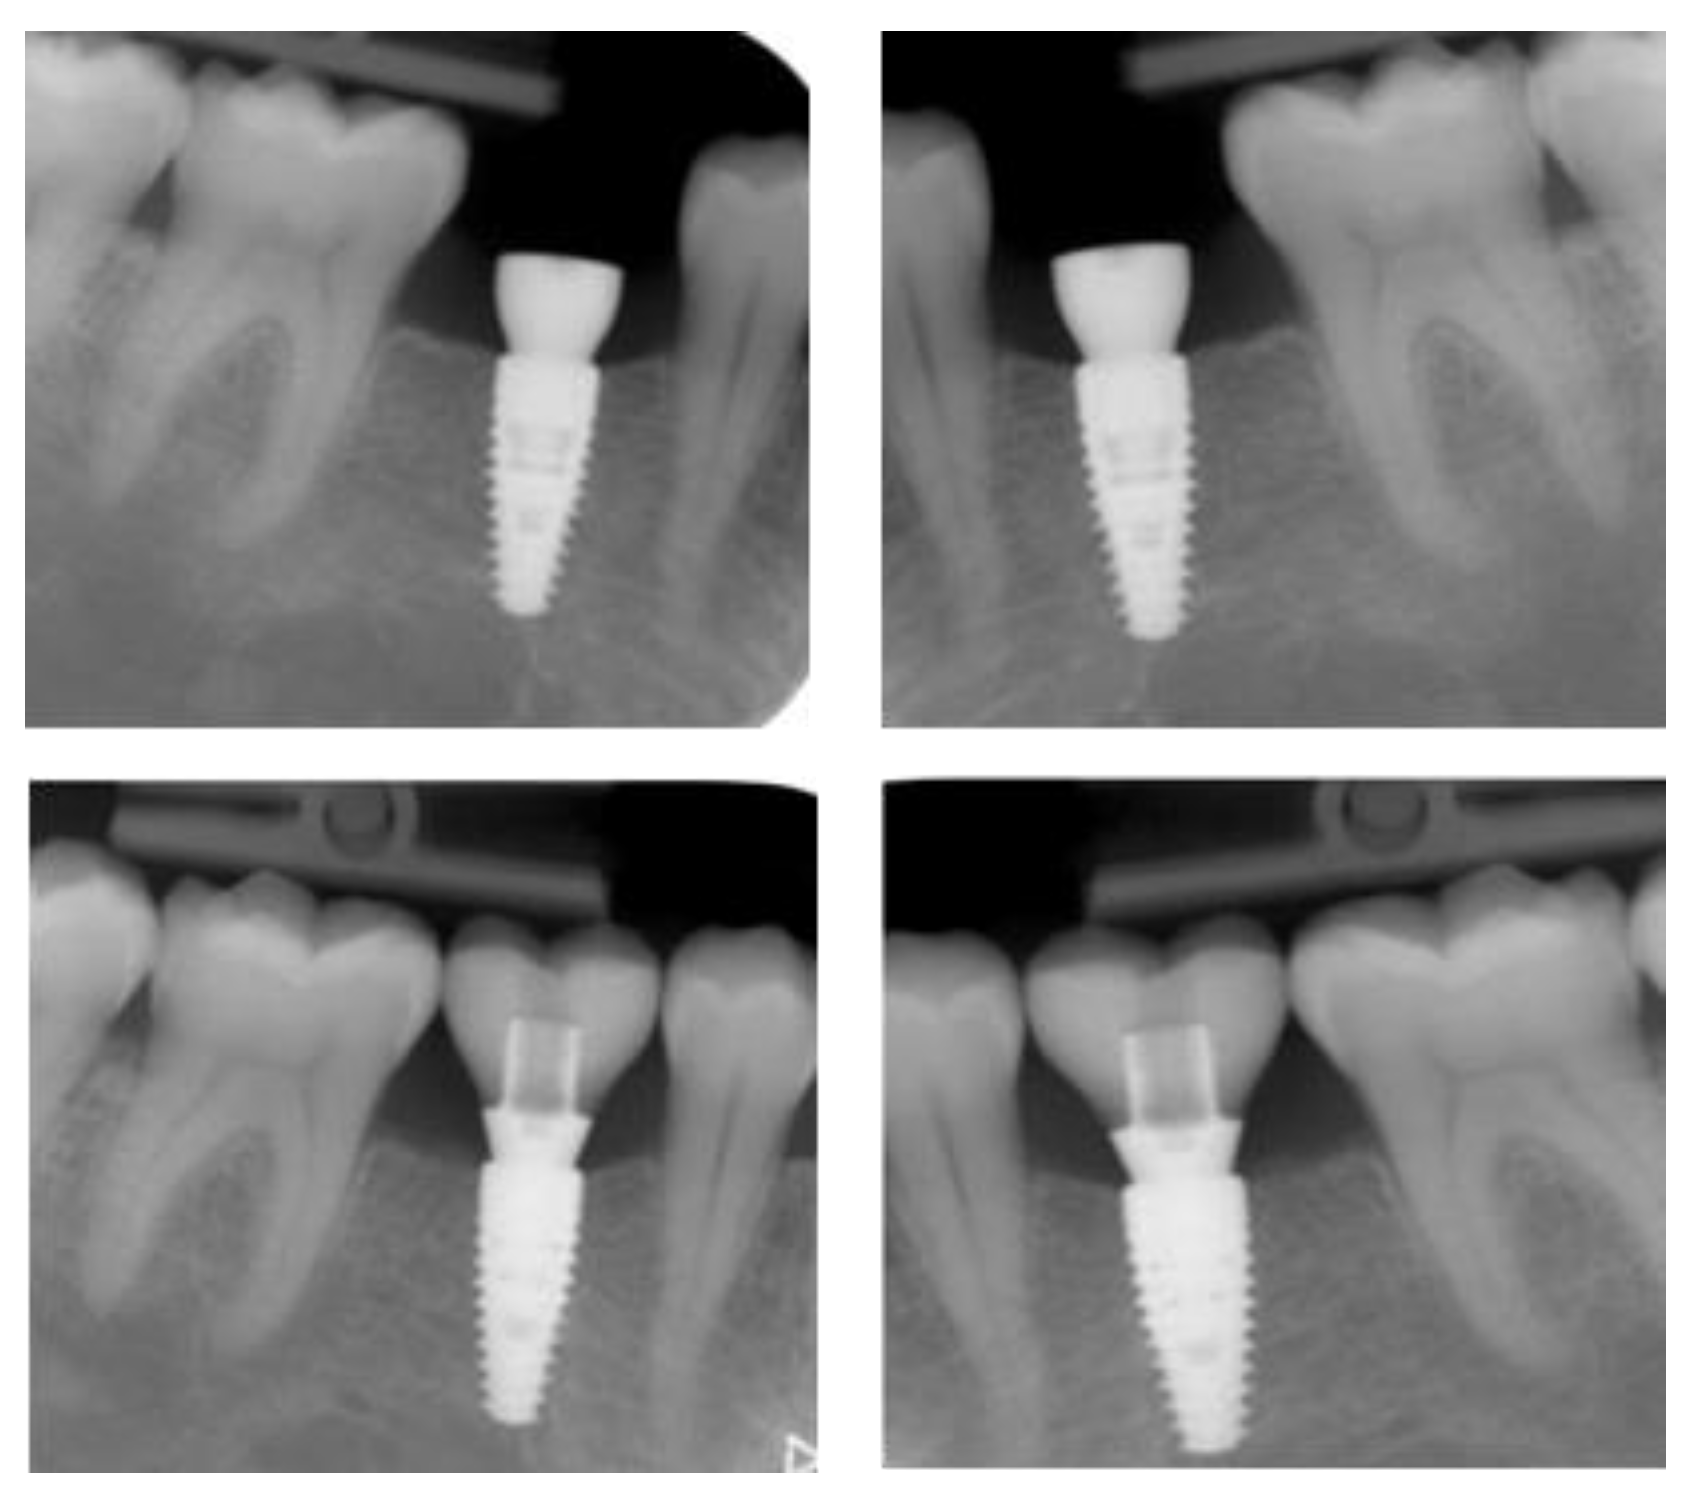

2.4.1. Radiographic Measurements

3.2. Marginal Bone Level Outcomes